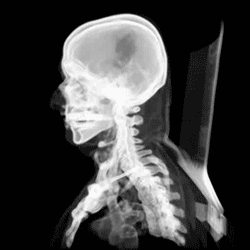

The skull, or cranium, is typically a bony enclosure around the brain of a vertebrate.[1][2] In some fish, and amphibians, the skull is of cartilage. The skull is at the head end of the vertebrate.

The skull is composed of three types of bone: cranial bones, facial bones and ossicles, which is made up of a number of fused flat and irregular bones. The cranial bones are joined at firm fibrous junctions called sutures and contains many foramina, fossae, processes, and sinuses. In zoology, the openings in the skull are called fenestrae, the most prominent of which is the foramen magnum, where the brainstem goes through to join the spinal cord.

In human anatomy, the neurocranium (or braincase), is further divided into the calvarium and the endocranium, together forming a cranial cavity that houses the brain. The interior periosteum forms part of the dura mater, the facial skeleton and splanchnocranium with the mandible being its largest bone. The mandible articulates with the temporal bones of the neurocranium at the paired temporomandibular joints. The skull itself articulates with the spinal column at the atlanto-occipital joint. The human skull fully develops two years after birth.